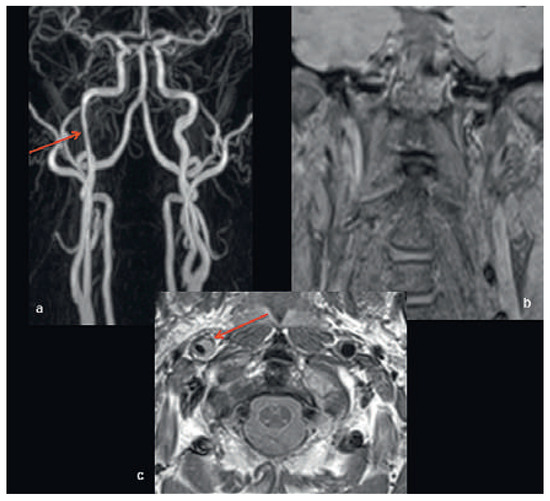

Head and brain trauma: general aspects and neuroimaging

by Johanna Maria Lieb, Christoph Stippich and Meritxell Garcia

Swiss Arch. Neurol. Psychiatry Psychother. 2015, 166(8), 279-292; https://doi.org/10.4414/sanp.2015.00374 - 1 Jan 2015

In this article the general clinical aspects, imaging indications and different injury mechanisms of traumatic brain injury (TBI) are reviewed. In addition, the different imaging modalities and strategies are presented, including more specific imaging features of the various injuries. Computed tomography (CT) is the imaging modality of choice in the acute phase owing to its wide availability and short scanning time, as well as to its high sensitivity for the detection of fractures and acute bleeding. Although magnetic resonance imaging (MRI) is superior to CT in many other aspects, it plays no role in the acute phase. MRI, however, has been proven to be useful and complementary to CT in the subacute and chronic stages as well as in the case of inconclusive results on initial CT. Especially the use of standard sequences like fluid attenuated inversion recovery (FLAIR), diffusion and susceptibility weighted imaging (DWI and SWI) have been shown to increase the diagnostic potency in diffuse axonal injury, in mild brain trauma and also in more chronic stages of TBI. The use of more advanced MRI techniques such as diffusion tensor imaging (DTI), magnetic resonance spectroscopy (MRS), functional MRI (fMRI) and magnetic transfer imaging (MTI) can further complete the diagnostic evaluation and give insights into different pathophysiological processes in TBI. Full article